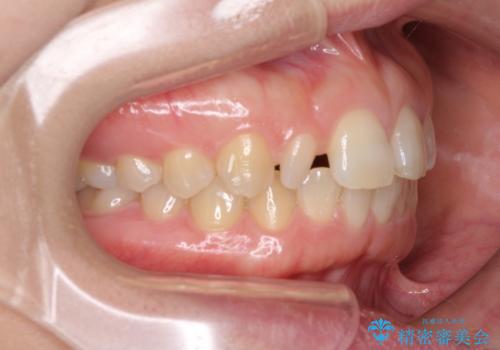

前歯の歯並びと小さい歯を改善 インビザラインとオールセラミッククラウン

- 前歯の空隙と矮小歯を気にして来院された患者様です。

上下の歯列不正はインビザラインにより整えることとしました。

矯正治療の後に、前歯1歯と奥歯をオールセラミックにて治療することとしました。

矯正治療により矮小歯前後にスペースを作りながら歯列を整え、セラミッククラウン装着後に最終的に歯列と咬合を仕上げました。